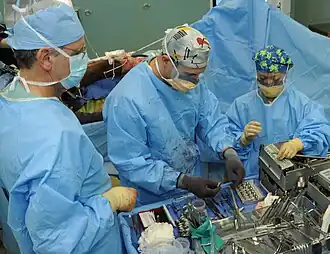

Internal fixation is an operation in orthopedics that involves the surgical implementation of implants for the purpose of repairing a bone, a concept that dates to the mid-nineteenth century and was made applicable for routine treatment in the mid-twentieth century.[1] An internal fixator may be made of stainless steel, titanium alloy,[2] or cobalt-chrome alloy.[3]

Open reduction internal fixation (ORIF) involves the implementation of implants to guide the healing process of a bone, as well as the open reduction, or setting, of the bone. Open reduction refers to open surgery to set bones, as is necessary for some fractures. Internal fixation refers to fixation of screws and/or plates, intramedullary rods and other devices to enable or facilitate healing. Rigid fixation prevents micro-motion across lines of fracture to enable healing and prevent infection, which happens when implants such as plates (e.g. dynamic compression plate) are used. ORIF techniques often are used in cases involving serious fractures such as comminuted or displaced fractures or, in cases where the bone otherwise would not heal correctly with casting or splinting alone.